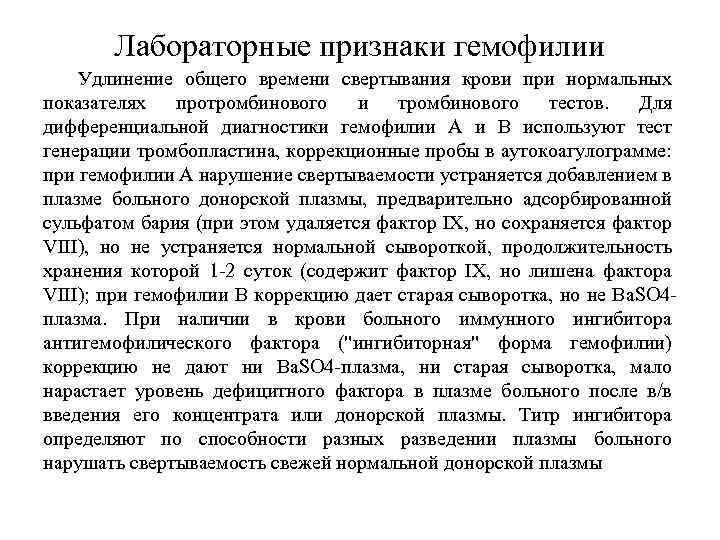

Лечение гемофилии Заместительная гемостатическая терапия криопреципитатом или концентратами фактора VIII (при гемофилии А) или фактор IX - препарат ППСБ (при гемофилии В). Показаниями к заместительной терапии являются кровотечения, острые гемартрозы и гематомы, острые болевые синдромы неясного генеза (часто связаны с кровоизлияниями в органы), прикрытие хирургических вмешательств (от удаления зубов до полостных операций). Лечение гемофилии основано на внутривенном введении дефицитного фактора свертывания крови. Терапия может либо предотвратить кровотечение, либо уменьшить его последствия